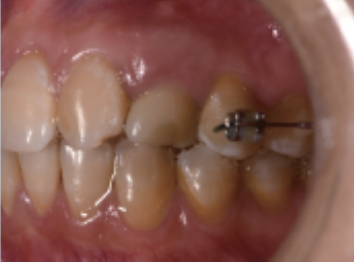

全口牙周情况良好,左上后牙正畸保持托槽固定,63滞留,松动(++),牙槽窝周围牙槽骨完整,

X线显示根尖周未见低密度影像,根尖区充足骨量;22先天缺失,23在22位置异位萌出,23与21邻接良好。

方法:患者轻咬合状态进行CBCT(NewTomTM,Verona,Italy)扫描,扫描结果以DICOM(digitalimagingandcommunicationinmedicine)格式导出。CBCT显示:左上乳尖牙牙根周围牙槽骨吸收,可用骨高度约15mm,颊舌径宽约6mm。